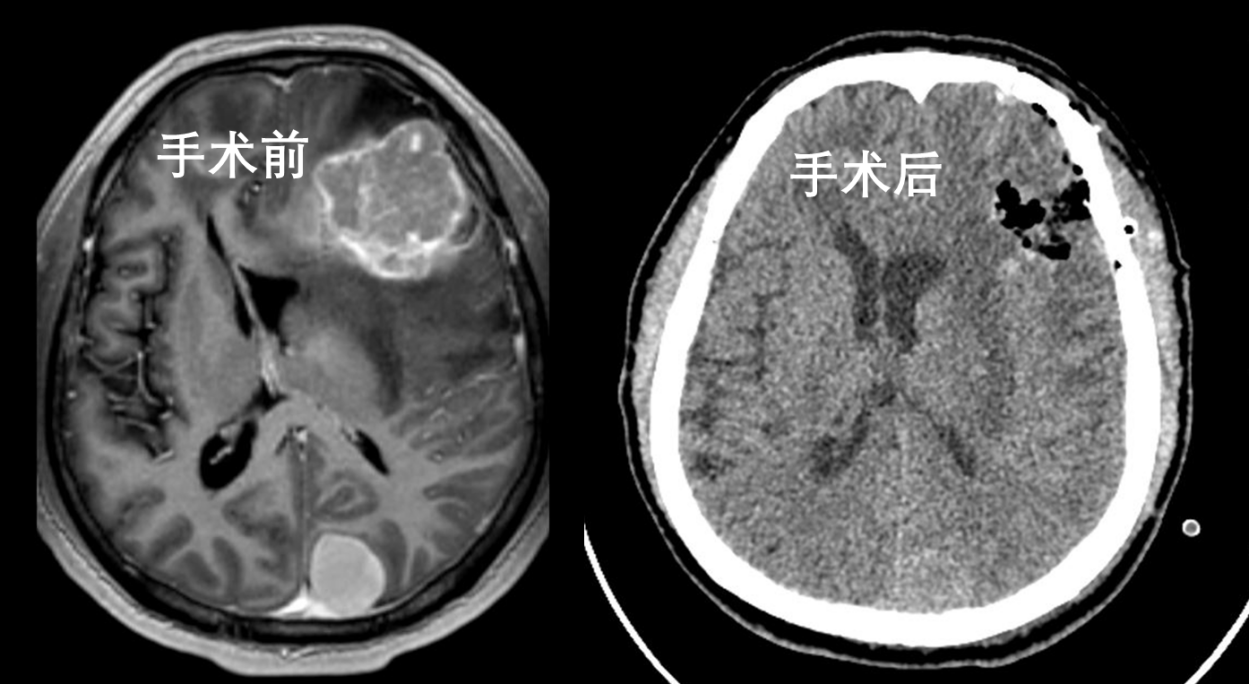

手术过程中,依据神经导航仪精准定位,巧妙避开功能区、血管,成功实现肿瘤全切。术后,李伯头痛、肢体乏力及癫痫症状完全消失。

借助三维重建技术,可清晰看到半透明化的头骨和脑组织,肿瘤与头骨上额窦、脑功能区的相对位置一目了然。

左额转移瘤术后第一天复查显示,肿瘤被全切,被挤压的脑室和脑组织成功复位。术后仅 1 周,他便能下地活动,生活实现自理。